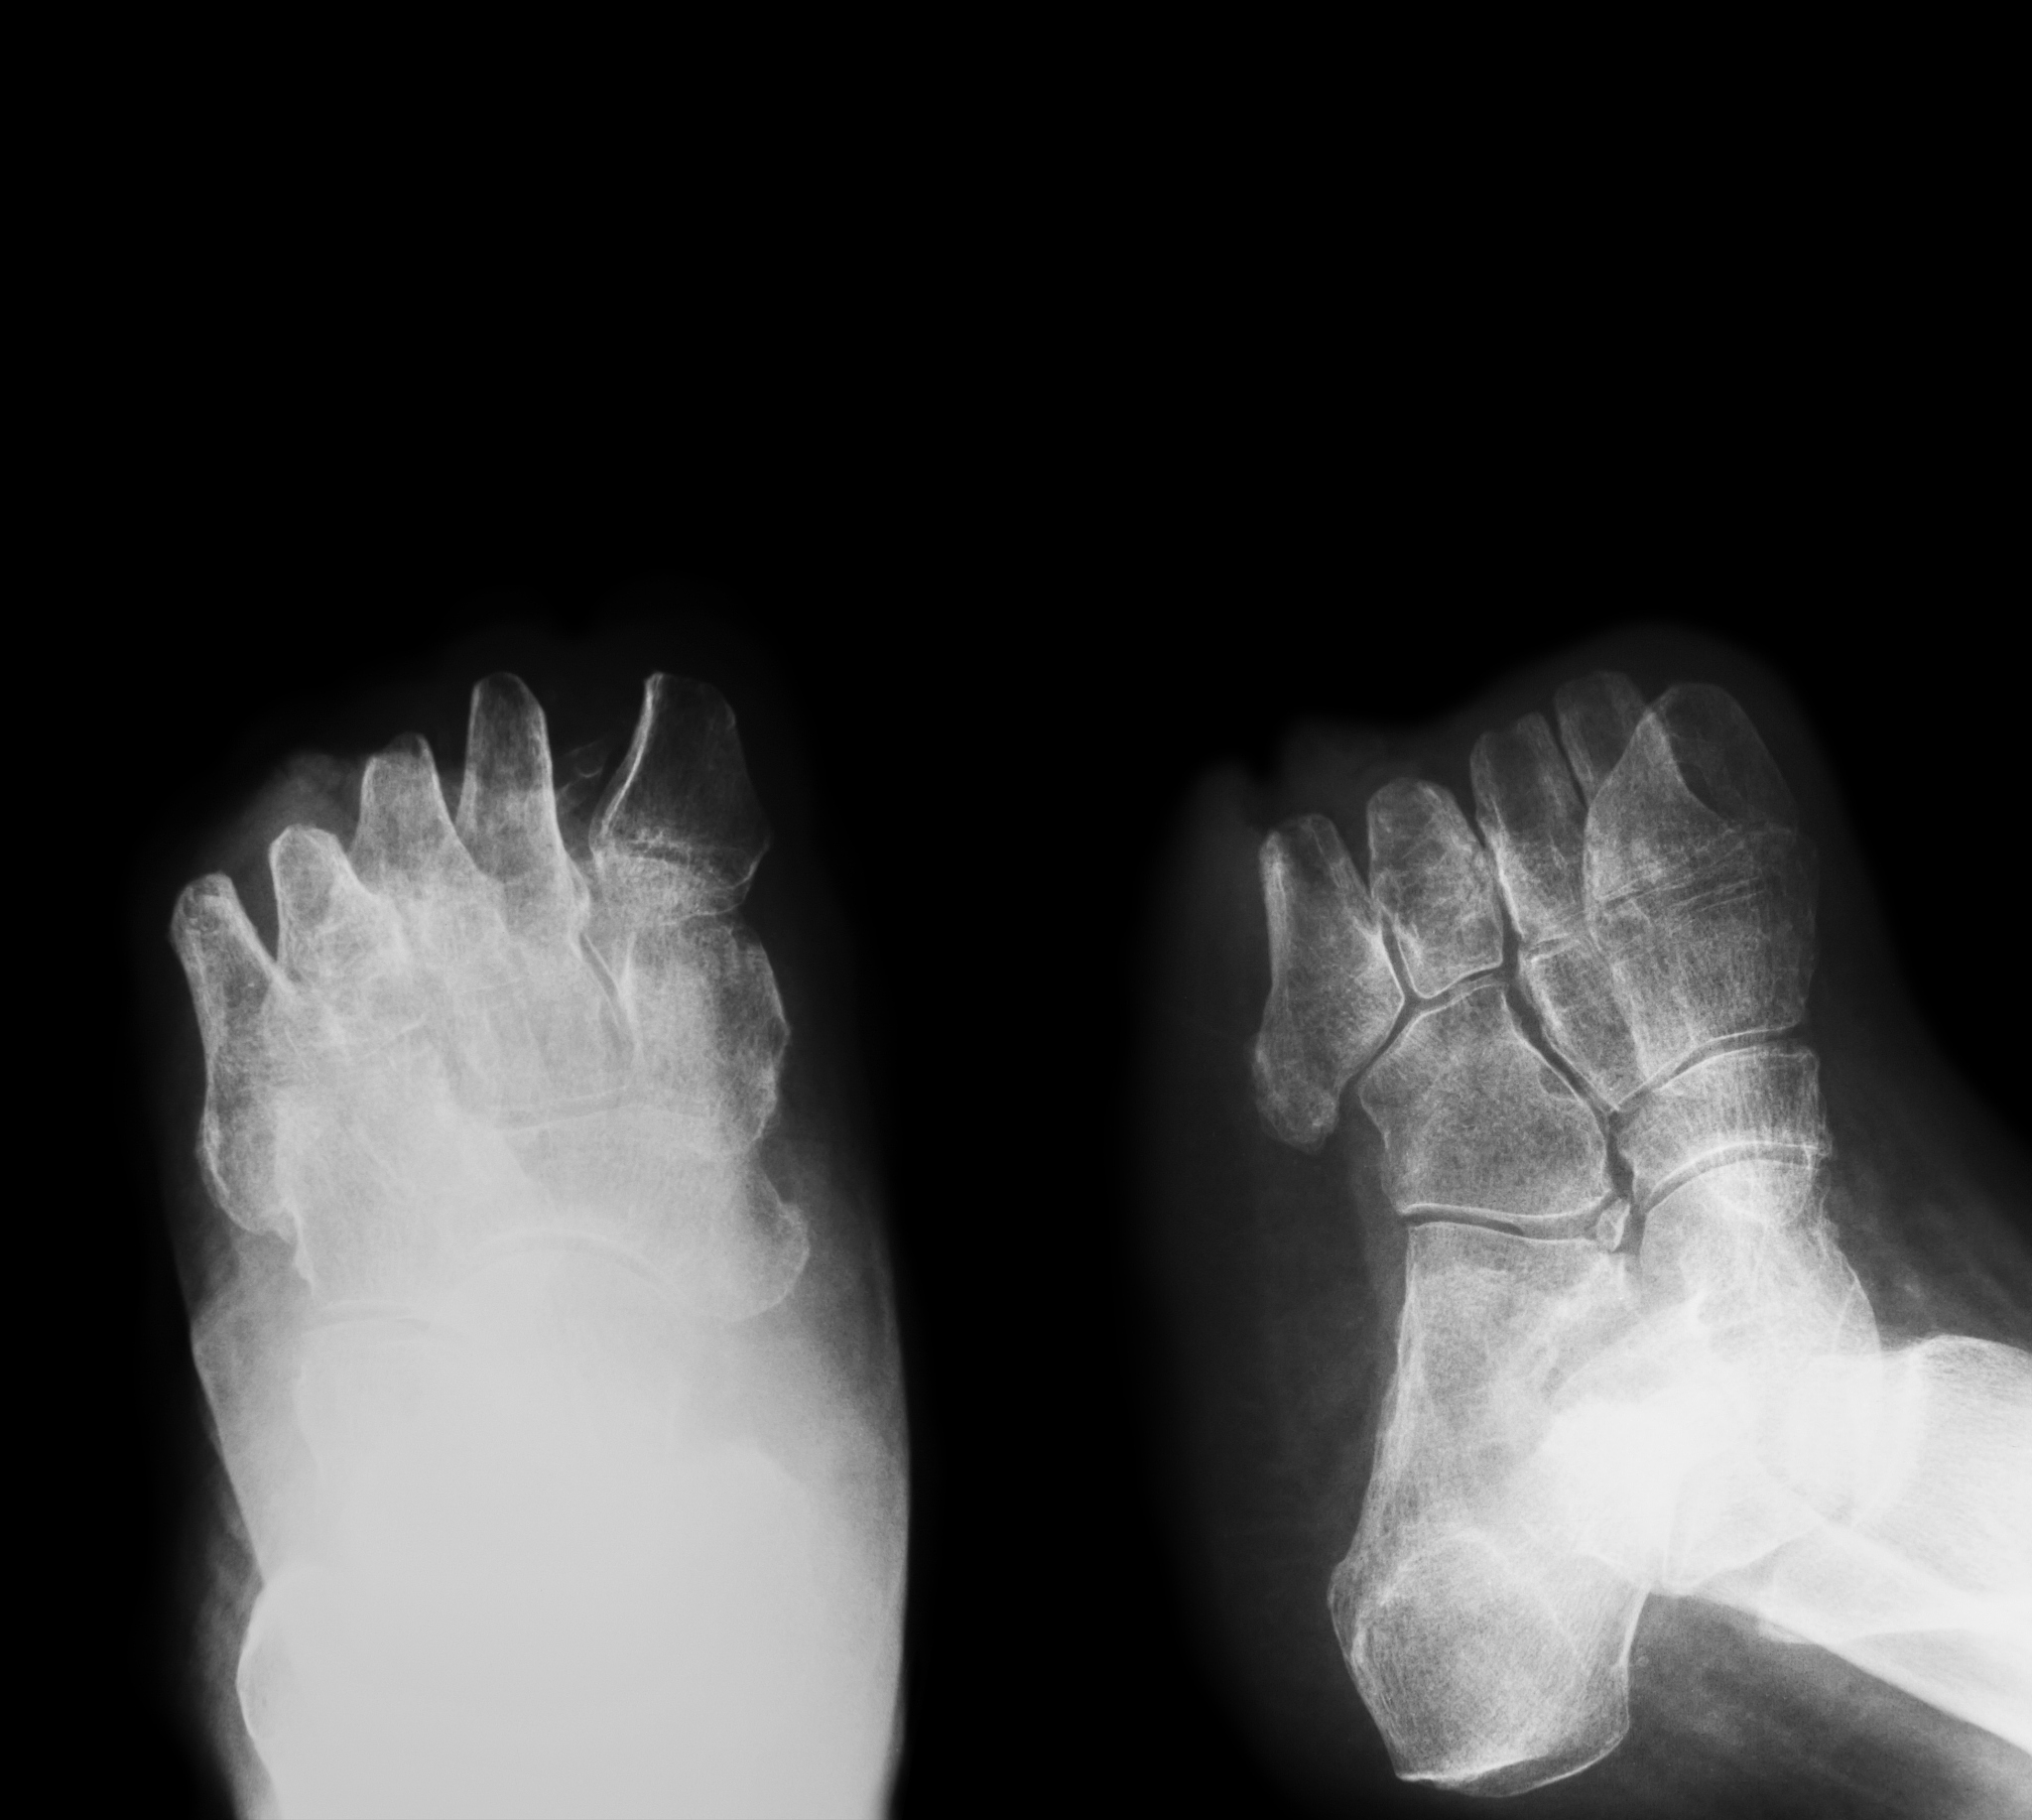

糖尿病足是指糖尿病患者由于长期高血糖导致的足部并发症。糖尿病足的主要原因是神经病变和血管病变,这使得患者对足部的疼痛和损伤感觉减退,同时也影响了足部的血液循环,容易引发感染和溃疡。